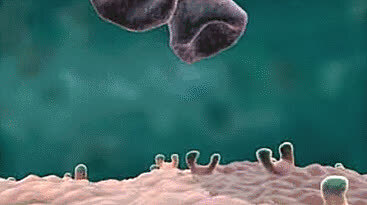

3.这是中性粒细胞追击金黄色葡萄球菌的一个过程。免疫细胞捕捉细菌时是不是超萌!

4.免疫细胞也可穿过血管壁奔赴“战场”,向炎症和创伤组织处进军、围剿。